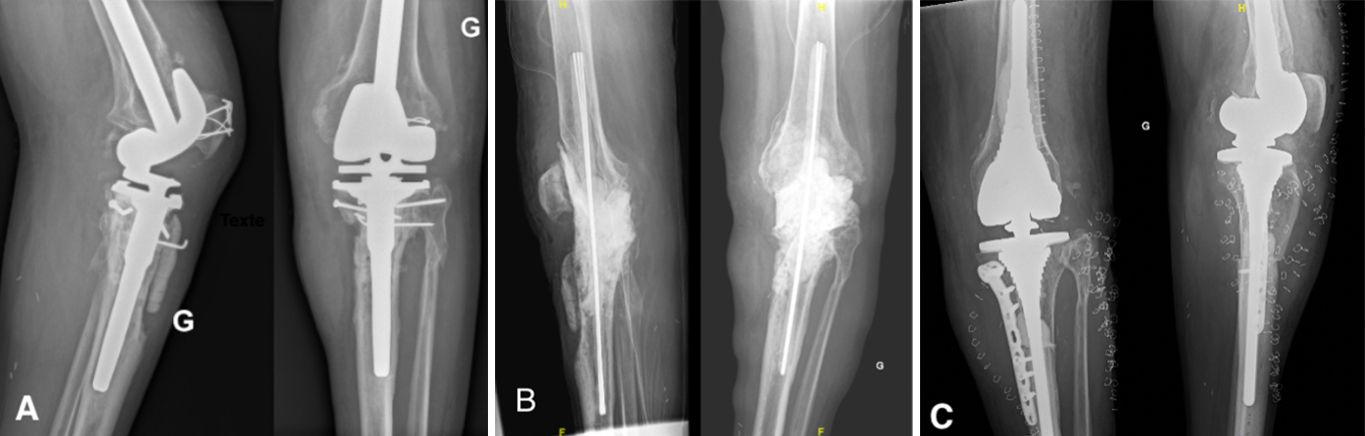

Antibiotic-impregnated cement spacers can be either static (non-articulating, block spacer) or dynamic [10]. Static spacers consist of a single block of cement inserted between the femur and the tibia (Case 1.B, 2.B, 3.B). It is non-articulating, fills the joint space and constitutes a temporary knee arthrodesis keeping the knee in full extension. This temporary immobilization leads amongst other things to joint stiffness and exposure difficulties at the time of reimplantation [9, 22, 23]. This increases the difficulty of prosthesis reimplantation and is associated with poorer clinical outcomes such as stiffness.

- Major bone loss, which is associated with a high risk of fracture, as well as a lack of fixation for a dynamic spacer (Cases 1-3).

- An incompetence of the collateral ligaments or the extensor mechanism, which can cause femoro-tibial dislocation with a dynamic spacer (Case 3).